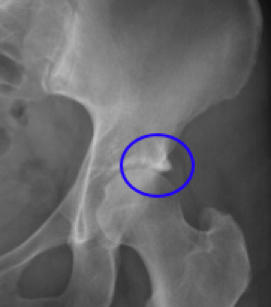

In the following two x-rays you can see a moderately severe case of pincer, in a 58 year old woman.

So too with Femoro Acetabular Impingement Syndrome Pincer. In the above mild case there is minimal hip arthritis. Tthe medical report states: There are no bony abnormalities in the pelvis In reality there is clear evidence of a pincer deformity bilaterally, as well as early sclerotic change in the left sacroiliac joint anatomy.